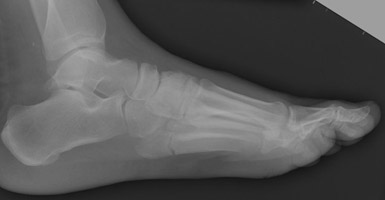

- Click on the image for a larger versionALateral radiograph of the foot. A patient stepped off a curb and sustained a fracture of the proximal aspect of the fifth metatarsal. According to Greenspan, this would be termed a "true Jones fracture."